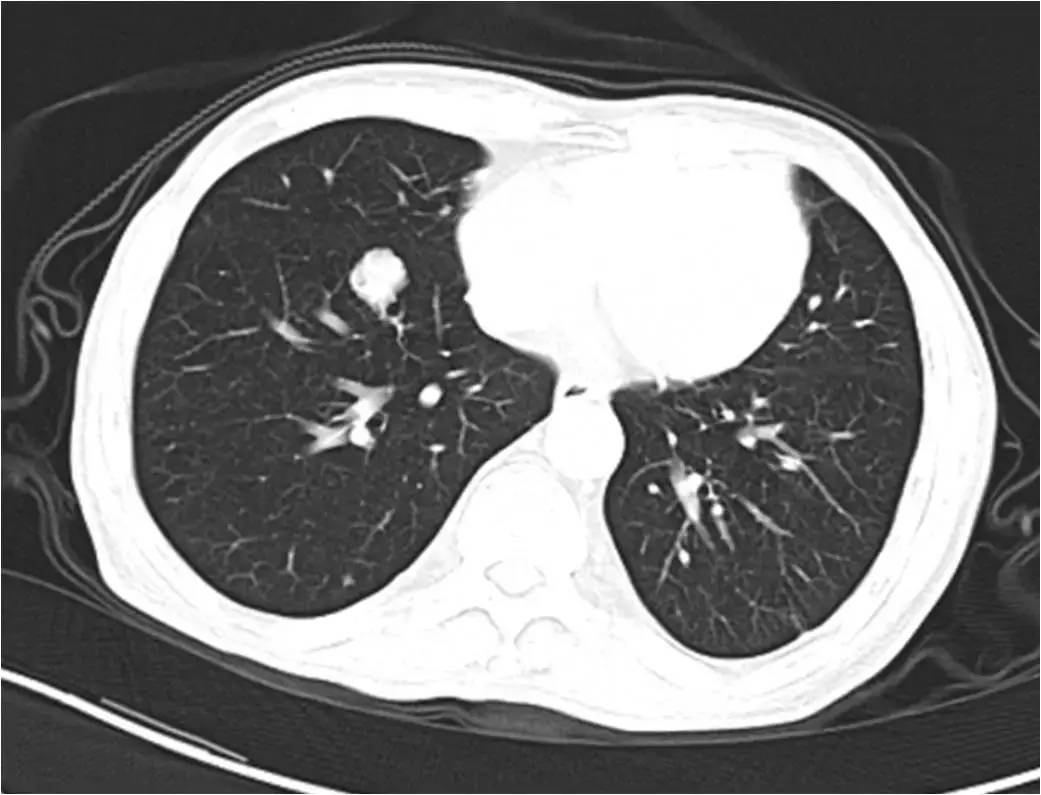

肺转移,肺转移瘤

肝癌并肺转移

肺癌或肺转移癌的微波消融术

肺转移癌的发生率与原发肿瘤的生物学特性和机体的免疫功能状态有关.

肺转移瘤

肺转移癌